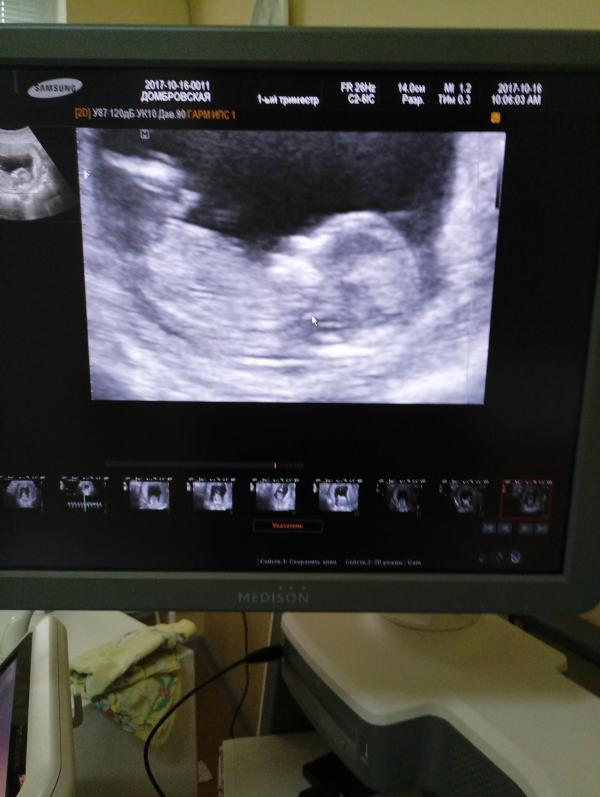

Не буду размусоливать, в общем всё хорошо)) Всё соответствует срокам, размеры все в норме. Осталось дождаться результатов крови. Предположили мальчика 😭, но сразу же сказали, что «пирамидки» 😄 у них щас одинаковые и ещё можно надеяться на девочку)) Главное, конечно, что всё хорошо, но мне позарез нужна девочка 🙈. А то эти, уже имеющиеся, три мужика дома, скоро сведут с ума 😂 Теперь полтора месяца до следующего узи. Ждём, растём, ожидаем шевелений!)